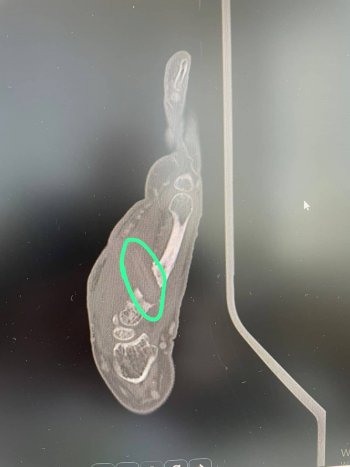

Gün geçtikçe elinin acısının arttığını ve elinin ön ve arka tarafının delinerek akıntı olmaya başladığını söyleyen Raziye Baş, “Kalça kırığı çok acı veren bir durum olmasına rağmen elimin acısından durmaz hale geldim. Tekrar hastaneye geldim. Günlerce hastanede yattım. Kolumdan film ve MR çekilmesine rağmen kimse bu film ve MR’a bakmadı. Enfeksiyon geçer diye tam 7 ay beklettiler. Kolumu kullanamaz ve yalnız başıma hayatımı sürdüremez hale geldim. Bir yakınımın tavsiyesi ile bu defa İzmir’e başka bir hekime gittim. Doktor beraberimde götürdüğüm film ve MR’ı bakar bakmaz içeride bir cisim olduğunu belirtip hemen ameliyata aldı. Elimin içinden büyük bir odun parçası çıkarıldı. Kısa sürede sağlığıma kavuştum” ifadelerini kullanarak bu duruma sebep olan kişi ve kişilerden şikayetçi olduğunu da ekledi.

İlk gittiği hastanede çekilen film ve MR’ı da paylaşarak yaşadığı acının normal bir sağlık sorunu olmadığını hatta tamamen ihmalden kaynaklandığını ileri süren Raziye Baş, “Ben ‘canım çok yanıyor elimi hareket ettiremiyorum’ dedikçe Aydın’daki doktor beni tembellikle suçladı. ’Tembel olduğun için elini hareket ettirmiyorsun’ deyip benim psikolojimi de bozdular. İnsan önündeki film ve MR’a bakmaz mı? Bana 7 ay boyunca adeta işkence ettiler” şeklinde sitem etti.